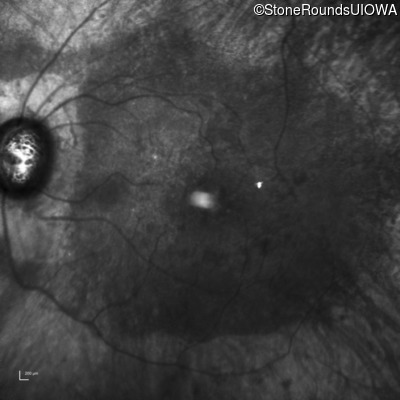

AR Retinitis Pigmentosa (IA1aiii)

Age at visit: 66 years

OD OS